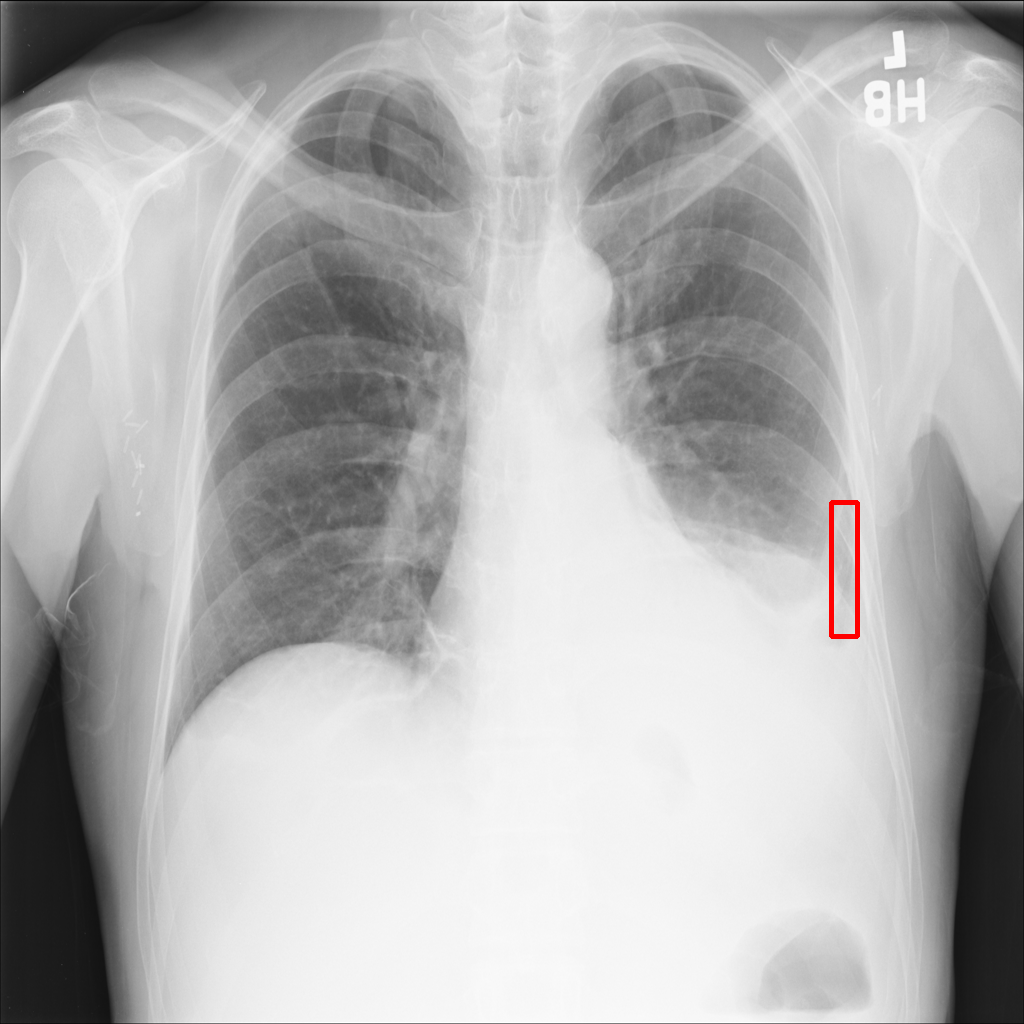

Object Rotation

X-ray GMAIMMbench Disease Diagnosis

Object Rotation - L0 (Original)

L0

L0 (Original)

Question

Given the boxed region in the X-ray image, which abnormality is the image most indicative of?

A pneumothorax B pulmonary fibrosis C bone fracture D pleural effusion

Ground Truth: A. pneumothorax